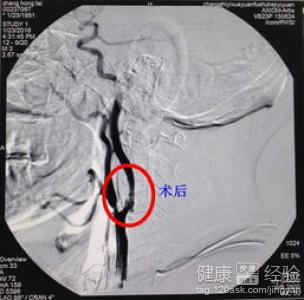

2在我們向周邊人了解的,關於股動脈穿刺的相關知識之後,對股動脈穿刺來說。穿刺針尖必須十分銳利,切緣光滑,穿透力強,從而易於一次刺入動脈壁。否則,穿刺針易在動脈鞘上滑動,造成穿刺失敗或增大血管壁的損傷。

3最後,關於股動脈穿刺來說,一根穿刺針常重復使用多次,因此,穿刺前應仔細檢查針尖是否銳利。具體方法是將針尖對准光源,銳利針尖無反光“亮點”,切緣無毛刺,反之則鈍。對老年、消瘦及動脈硬化患者應選用新針穿刺,提高一針穿刺成功率。